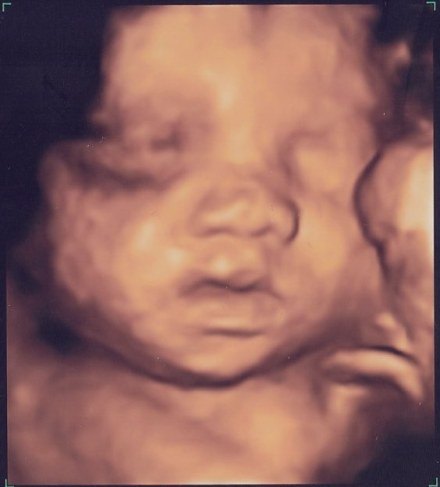

Vi glæder os sådan til at møde hende. Hende med fars næse og mund, hende som de siger har masser af hår på hovedet. Vores lækre lille halvkoreanske skønhed! Vores prinsesse, solskin og lille mirakel

Fra streger, til første mave, til NF til 3D til stor mave!